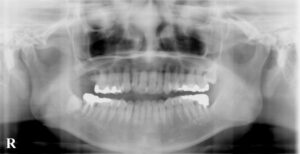

2010年1月 右上第二大臼歯の違和感で来院

2011年9月に 詰め物が外れたという訴えで来院され

同年の12月に同部の痛みが激しくなり来院

2014年4月 同部の手前の歯の詰め物が外れたと来院

同年の7月に、今回の自費と比較する

保険診療の題材となる左下第二大臼歯

の痛みに対処するために

2015年8月に反対の右下第二大臼歯の痛みで来院され

2017年8月 再来時に左下第二大臼歯のレントゲン

2020年6月 右上第一大臼歯の問題をご本人が訴え

レントゲンを撮影し以前と比較説明してから

レントゲンでは神経の詰め物の状態の違い→

歯根の崩壊度は経時的なもの?→